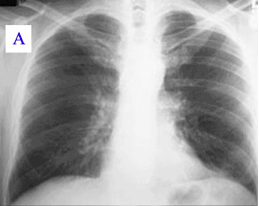

Otprilike polovina zaraženih osoba ne pokazuje simptome. Tokom svog razvoja bolest može preći u atipičnu upalu pluća, što može rezultirati akutnim respiratornim distres sindromom opasnim po život, pri čemu se takvi simptomi obično javljaju u prva četiri do pet dana infekcije.

Problemi sa plućima - neki ljudi koji imaju Q groznicu razvijaju upalu pluća. To može dovesti do akutnog respiratornog distresa.